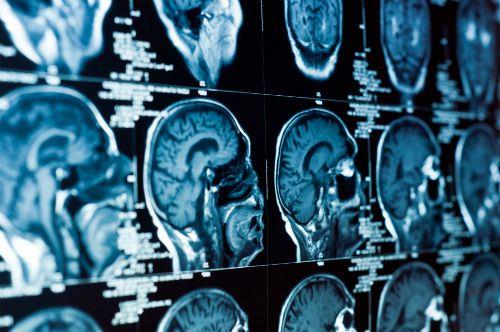

כדי לחקור את אופי הסינכרון במוחותיהם של אלה הנמצאים על הספקטרום האוטיסטי, השתמשו החוקרים במאגר נתונים של דימות תפקודי בתהודה מגנטית (fMRI), שנאסף ממספר רב של נבדקים שהיו במצב מנוחה. "התמקדנו בפעילות מוחית בזמן מנוחה", אומרת חכמי, "כיוון שהיא נוצרת באופן ספונטני, ומאפשרת להבין כיצד אזורי המוח השונים פועלים ומסונכרנים באופן טבעי". מחקרים קודמים שהתבצעו בקבוצתו של פרופ' מלאך, וכן בקבוצות מחקר אחרות, מציעים כי הפעילות המוחית הספונטנית עשויה לשקף תכונות התנהגותיות אישיות, לרבות אלה המבטאות אורח חיים יחודי.

כאשר השוו החוקרים בין הפעילות המוחית הספונטנית של הנבדקים האוטיסטים לבין זו שהתקבלה מקבוצת הביקורת (שלא כללה אוטיסטים), הם גילו תופעה מעניינת. בעוד שתבניות הסינכרון של הפעילות המוחית היו דומות בין נבדקים שונים של קבוצת הביקורת, במוחות הקבוצה האוטיסטית נמצאו תבניות שונות וייחודיות – כל אחת בדרכה. במילים אחרות, תבניות הפעילות המוחית שנצפו בקבוצת הביקורת ייצגו פעילות מוחית "קונפורמיסטית" ביחס לפעילות המוחית של הקבוצה האוטיסטית, בה כל מוח ייצר תבנית שונה ומיוחדת. הבדלים אלו בין הקבוצות יכולים להתבטא בחוסר סינכרון או עודף סינכרון באזורים שונים במוח האוטיסטי, כפי שנמצא במחקרים קודמים.